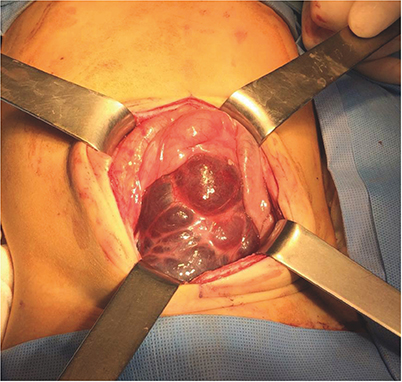

Of the 12 patients, 4 had lesions located in the retroperitoneum, 4 had lesions in the greater omentum, 2 had lesions in the mesentery of the jejunum, and 2 had lesions in the retroperitoneum and mesentery. Lesion size ranged from 7×3.5 cm to 30×15 cm (Table 1). Seven patients underwent surgery including 3 who underwent laparoscopic resection. An additional 3 patients (Nos. 2, 5, and 7) underwent lesion resection, along with segmental resection of the adjoining bowel and end-to-end anastomosis (Fig. 3). In 2 patients (Nos. 8 and 9), the mass was incompletely resected because the lesions were extensive and invaded the superior mesenteric artery and vein (Fig. 4). None of the 12 patients experienced postoperative complications. After a postoperative follow-up period of 8–183 months (median, 50 months), only 1 patient (No. 6) experienced lesion recurrence. The cystic mass in the greater omentum of this patient was completely resected laparoscopically, but abdominal ultrasonography 7 months later showed a recurrent lesion, 4 cm in size. Although surgical treatment was recommended, the child's parent refused surgery. An abdominal CT scan 1 year after surgery revealed a slight decrease in lesion size, but the patient was subsequently lost to follow-up (Table 2). In contrast, abdominal ultrasonography of patients No. 8 and 9, who underwent incomplete resection, showed no evidence of residual lesions or recurrences 52 and 48 months after surgery, respectively.

Fig. 3

Photograph of the 9 cm sized round cystic mass removed from patient No. 7. The mass originated from the jejunal mesentery and stretched the adjoining jejunum.